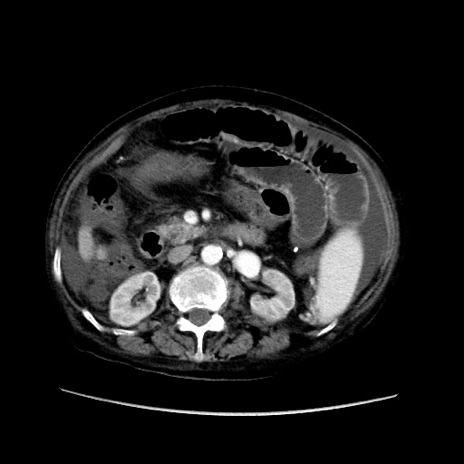

症例31(横断像)

【症例】80歳代 女性

【主訴】腹部膨満感

【現病歴】他院にて肝硬変にてフォロー中。1週間前から便秘、腹部膨満感、臍部腫瘤あり受診となる。

【既往歴】肝硬変

【身体所見】腹部膨隆あり、皮膚変化なし、疼痛なし。

【データ】WBC 4600、CRP 0.25